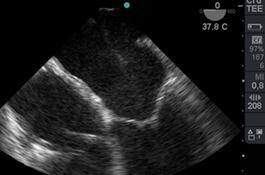

Valoración con ETE(21): Luego de la inducción anestésica colocamos la sonda y comenzamos a realizar una valoración completa del corazón logrando las 28 imágenes recomendadas por las guías actuales para realizar un exámen completo(22), luego valoramos la morfología y función de la válvula mitral en 2D desde medioesofágico 4,3 y 2 cámaras, y transgástrico a 0° y 90°. El principal objetivo, es corroborar los hallazgos preoperatorios y realizar un completo exámen cardiovascular, para documentar el estado cardíaco basal, funciones sistólicas(21) y diastólica(22), presión de arteria pulmonar, estado de la función cardíaca derecha y analizar las otras válvulas cardíacas en busca de anomalías no detectadas en el preoperatorio.